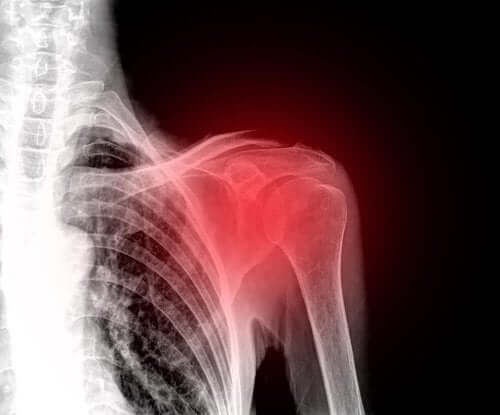

回旋筋腱板断裂について知っておくべきこと

回旋筋腱板断裂は、中高年の肩に頻繁に起こる怪我です。昨今では、肩の痛みの主要な原因の1つです。

回旋筋腱板断裂とは

この部位の断裂は、年間10万人のうち約4人に起こると言われます。

回旋筋腱板断裂の症状

重症度によって症状は異なりますが、主な症状は肩の痛みです。同様に、この関節のすべての動きが制限されます。